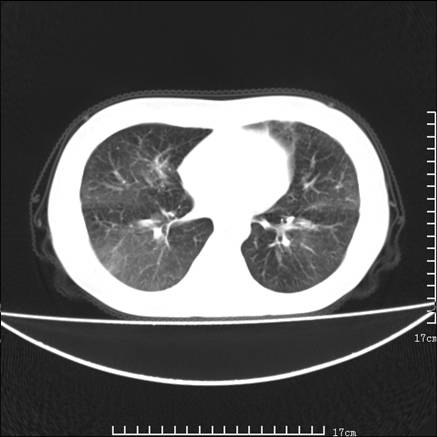

女,46岁,患胃溃疡多年,溃疡大小约1.0cm左右,后于5年前手术,病理为胃癌。主诉:半月前感冒后胸闷,气短,有咳嗽,无明显咳痰,无发热。偶有腰背部不适。

以下为高分辨扫描图像

双肺小叶间增厚,双肺散布粟米影和磨玻璃状影,以双肺上叶为重。结合病史考虑转移(癌性淋巴细管炎)可能性大。

结合病史:认为是典型肺部癌性淋巴管炎、淋巴结转移。请看图解。